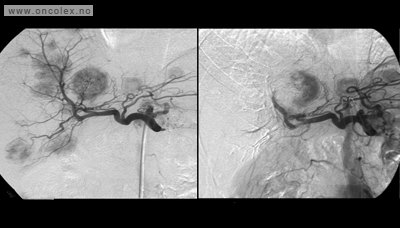

Det gis lokalbedøvelse. Røntgenlegen fører et kateter inn til pulsåren til leveren via pulsåren i lysken. For å tette arteriene sprøytes små partikler inn gjennom kateteret. Behandlingen kan vare fra 30 minutter og opp til flere timer. Til slutt kontrolleres resultatet med angiografi, og innstikkstedet i lysken lukkes.

Etter operasjonen kontrolleres pasienten med CT eller MR. Dette gjøres vanligvis 6 måneder etter inngrepet.